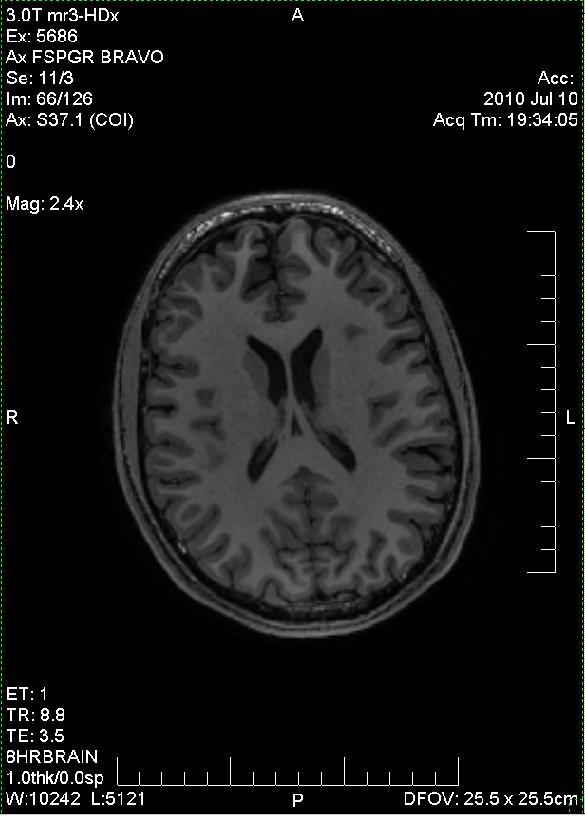

fMRI הוא מתקן המבוסס על תהודה מגנטית (לא קרינה) ומאפשר סריקה לא פולשנית של רקמות פנימיות. זה מכבר ידוע שחלה זרימה מוגברת של דם לרקמות "פעילות" לעומת רקמות "במנוחה" בגוף. הדבר תקף לרקמות מוח (נוירונים) כמו גם לרקמות אחרות. בעת פעילות כלשהי, הנוירונים האקטיביים במוחנו צורכים יותר חמצן מנוירונים שאינם פעילים. תאי הדם האדומים נושאים את החמצן על ידי קשירתו להמוגלובין אל הרקמות בהן הוא דרוש. המוגלובין בדם עשיר בחמצן מגיב אחרת למגנטיות מאשר המוגלובין בדם דל בחמצן. ההבדלים בין המשיכה המגנטית לדחייה המגנטית הם מזעריים, אך ניתנים למדידה. מכשיר ה-fMRI מודד את אותה תהודה מזערית של המגנטיות ברקמות השונות, ומאפשר לבנות תמונה של הרקמה ולהצביע על מוקדים פעילים במיוחד.

כמובן שאיחרתי לשוב הביתה וזוגתי נאלצה לארח למשך שעה שלמה את כל החבורה שהגיעה בלעדיי, מסבירה להם שאני משועמם כל כך שהלכתי לסרוק לעצמי את המוח. בסך הכל ביליתי בבית החולים כשלוש שעות, מתוכן בתוך מכונת ה-fMRI כשעה וחצי, חתמתי על חמישה או שישה טפסים ביורוקרטיים, עניתי על ארבעה מקבצי מבחנים פסיכולוגיים שונים תוך כדי סריקה, ביצעתי שני מיפויים נלווים (סריקה אנטומית ו"צפיפות החומר הלבן" במוחי), מעל 1600 "חתכי מוח" נלקחו תוך כדי פתרון השאלות, ושתיים וחצי אצבעות ביד ימין נרדמו לי. לסיכום, היה זה "קרוב להפליא רועש להחריד" - ממש כמו כותרת ספרו של ג'ונתן ספרן פויר. אבל קשה לי לחשוב על דרך טובה יותר לסיים את הסמסטר הזה. וחוץ מזה – מה לא עושים בשביל המדע?